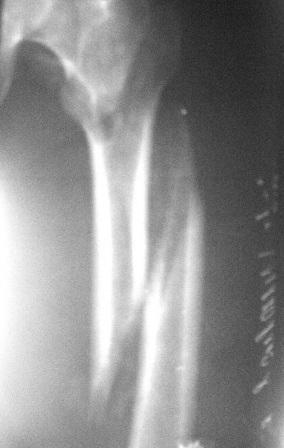

Вертельный перелом уже срастается в приемлемом положении отломков. Для сохранения шеечно-диафизарного угла в проксимальной опоре аппарата по оси шейки можно ввести 2-3 стержня.

Лучше сделать остеоклазию на уровне диафиза секциями аппарата (ротацией), затем проводить дистракцию темпом 2-4 мм/сут дробно, в пределах переносимости пациентом. После восстановления длины и сопоставления диафиза по оси закрыто заштифтовать. Имеющийся стержень вполне подойдет, поскольку вертельный перелом уже не будет требовать остеосинтеза.